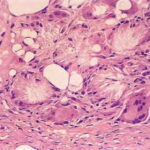

Histopathology. Focal areas of fat necrosis are present in the fat lobules and are infiltrated by macrophages and foreign body-type giant cells (Fig. 20-28). Fat deposits in the macrophages and giant cells contain crystalline fat, which after lipid extraction appears as needle-shaped clefts in a radial arrangement . In frozen sections, the radial clefts contain doubly refractile crystals. Calcium deposits usually are small and scattered in the necrotic fat. If the necrosis is |

extensive, calcium deposits may be large and require several years to be reabsorbed. |

Pathogenesis. Electron microscopic examination shows that the phagocytosis of fat crystals starts with the invasion of fat cells by cytoplasmic projections of macrophages. Subsequently, fat crystals are seen within the cytoplasm of macrophages and of foreign body-type giant cells, which result from fusion of the macrophages . |